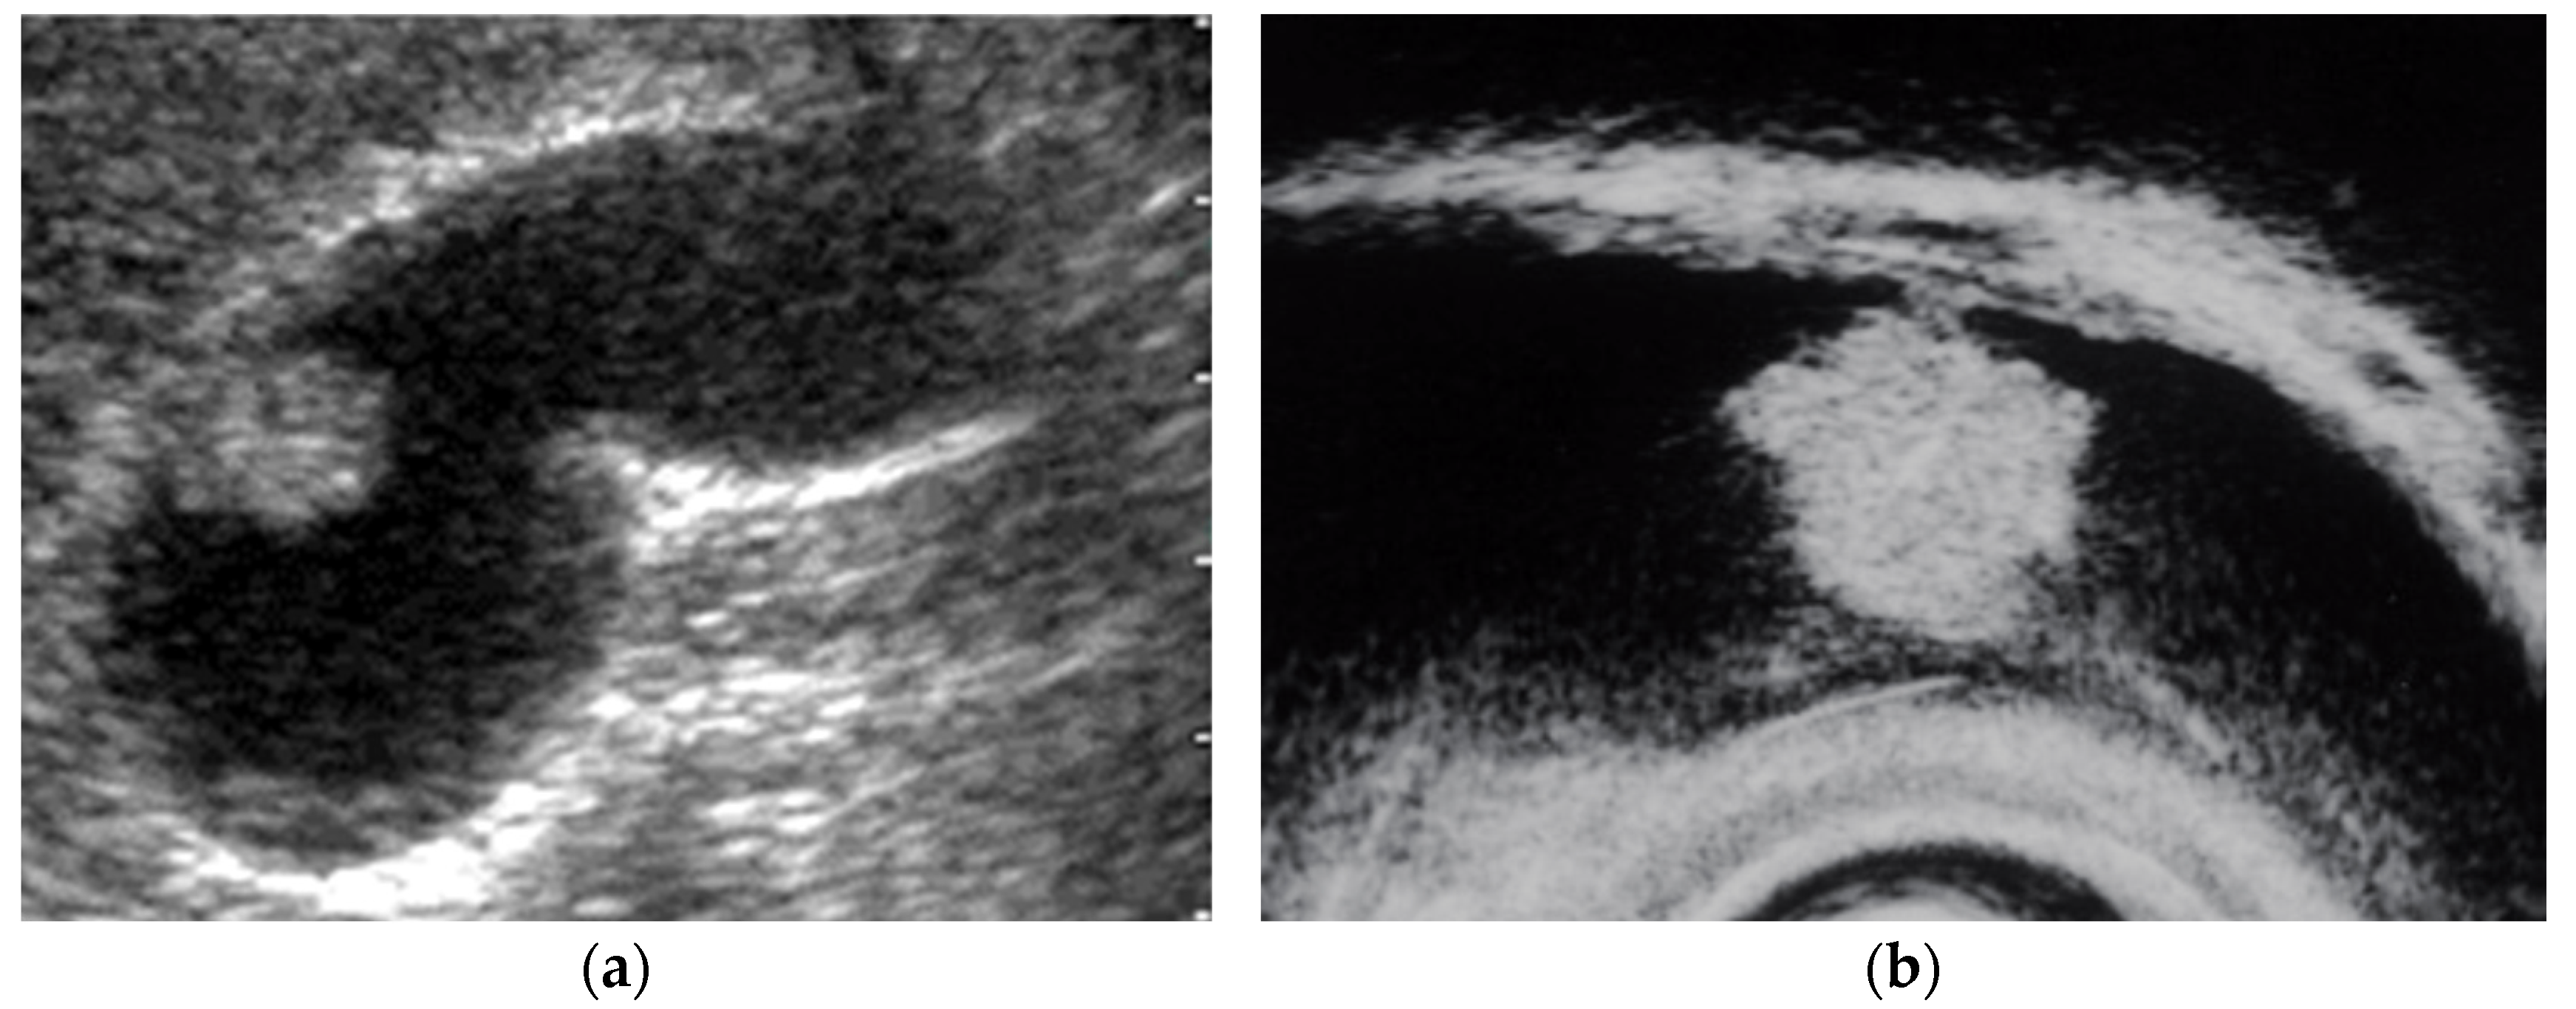

- Cho, J.H.; Park, J.Y.; Kim, Y.J.; Kim, H.M.; Kim, H.J.; Hong, S.P.; Park, S.W.; Chung, J.B.; Song, S.Y.; Bang, S. Hypoechoic foci on EUS are simple and strong predictive factors for neoplastic gallbladder polyps. Gastrointest. Endosc. 2009, 69, 1244–1250. [Google Scholar] [CrossRef]

- Cocco, G.; Basilico, R.; Delli Pizzi, A.; Cocco, N.; Boccatonda, A.; D’Ardes, D.; Fabiani, S.; Anzoletti, N.; D’Alessandro, P.; Vallone, G.; et al. Gallbladder polyps ultrasound: What the sonographer needs to know. J. Ultrasound. 2021, 24, 131–142. [Google Scholar] [CrossRef]

- Sadamoto, Y.; Oda, S.; Tanaka, M.; Harada, N.; Kubo, H.; Eguchi, T.; Nawata, H. A useful approach to the differential diagnosis of small polypoid lesions of the gallbladder, utilizing an endoscopic ultrasound scoring system. Endoscopy 2002, 34, 959–965. [Google Scholar] [CrossRef]

- Choi, W.B.; Lee, S.K.; Kim, M.H.; Seo, D.W.; Kim, H.J.; Kim, D.I.; Park, E.T.; Yoo, K.S.; Lim, B.C.; Myung, S.J.; et al. A new strategy to predict the neoplastic polyps of the gallbladder based on a scoring system using EUS. Gastrointest. Endosc. 2000, 52, 372–379. [Google Scholar] [CrossRef]